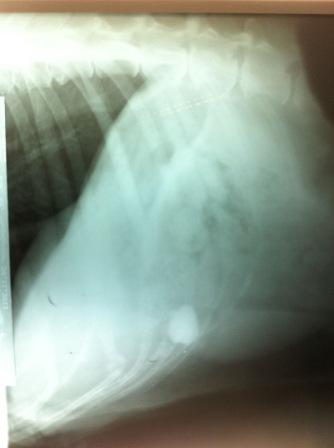

Die kleinwüchsige Schäferhündin Hagebutte übernahmen wir im Alter zwischen 10 und 14 Jahren. Sie war vom Welpenalter an kurz angekettet, so dass sie sich nie bewegen, nie laufen, nie spielen konnte, sondern ihr ganzes Leben von der kurzen Kette so beengt verbringen musste, dass sich ihre Muskulatur nicht entsprechend ausbilden konnte und sie nicht ganz „rund“ geht. Auch hat sie einen großen Tumor am Bein und an der Brust und hatte von Stechfliegen blutig abgefressene Ohren. Ihr Herz ist noch recht gut, doch das Röntgenbild zeigte Steine und Metallteile im Magen, die die arme Hündin im verzweifelten Hunger verschlungen haben muss. Inzwischen hat sich ihre Magen der Metallteile entledigt, jetzt ist "nur" noch ein Stein zu sehen. Das zeitlebens nur geschundenes Hagebuttchen ist nur lieb, freundlich und sanft. Unbegreiflicherweise liebt sie alle Menschen, verträgt sich auch mit Hunden bestens und tut auch keiner Katze was zuleide.